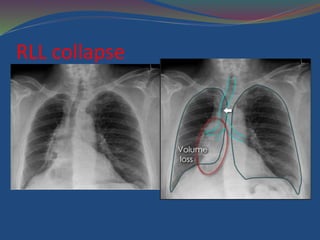

Lower Lobe Collapse

 The pattern of collapse is similar for both lower lobes,

which collapse caudally, posteriorly, and medially toward

chest x-ray of RLL collapse

 Tracheal deviation to the right

 overall volume loss of the right hemithorax, compared

with the left.

 The mediastinum is therefore PULLED to the right.

RLL collapse